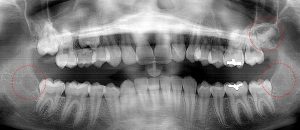

This 19 year old patient has all four 3rd molars present (circled). The roots are +90% formed. Both lower 3rd molars are impacted against the 2nd molars with no chance of further eruption and a +60% probability of decaying before age 30. The patient presented with pain and infection around both lower 3rd molars, requiring immediate extraction